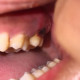

Alo dokter. Pasien sy berusia 25 tahun mengeluhkan Muncul bekuan darah pada gusi gigi 27, riwayat pencabutan gigi 28 pada 4 hari yg lalu. Pasien merasakan nyeri pada bekuan tersebut jika tersentuh. Ini bekuan darahnya disebabkan krn apa yah dok? Terima kasih dok